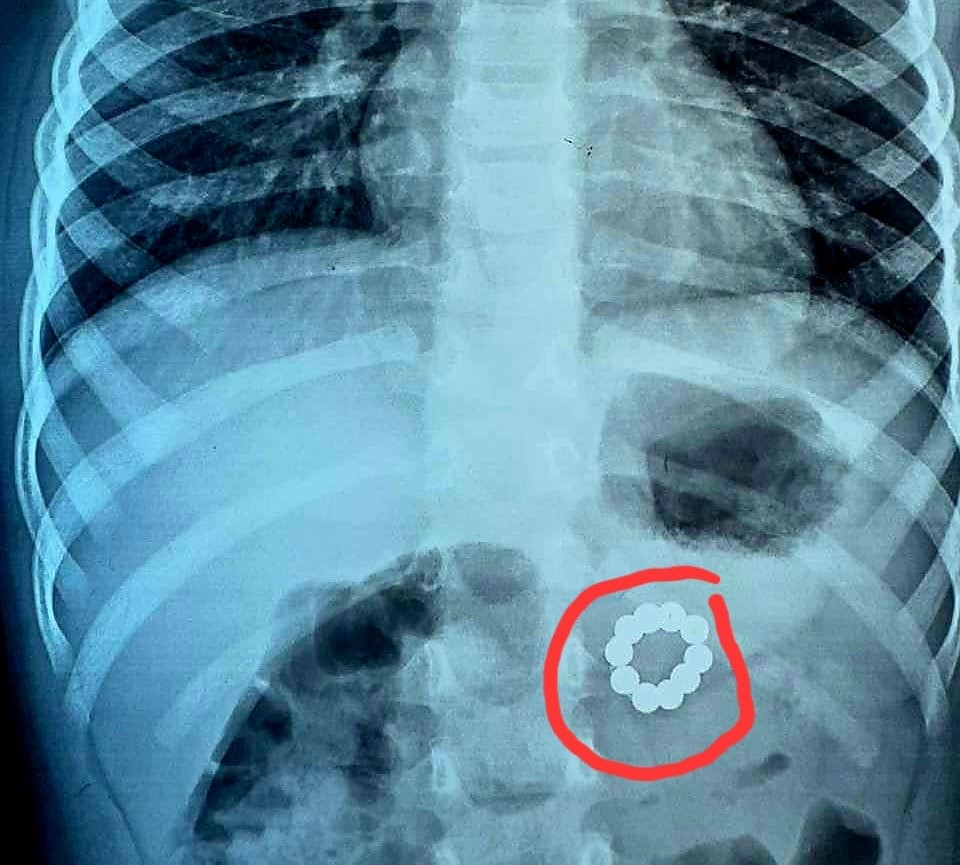

В Івано-Франківську зі шлунково-кишкового тракту трирічної дитини видалили 21 неодимовий магніт (ФОТОФАКТ)

Медики Івано-Франківської обласної дитячої клінічної лікарні видалили 21 неодимовий магніт зі шлунково-кишкового тракту трирічної дівчинки.

При обстеженні на догоспітальному етапі в шлунково-кишковому тракті пацієнтки виявили неодимові магніти.

Видалення ендоскопічно не було можливе, тому провели оперативне втручання, під час якого видалили десять магнітів з товщі задньої стінки шлунку і ще 11 — з початкового відділу здухвинної кишки.

З додаткового анамнезу виявили, що магніти були в ШКТ дитини понад місяць.